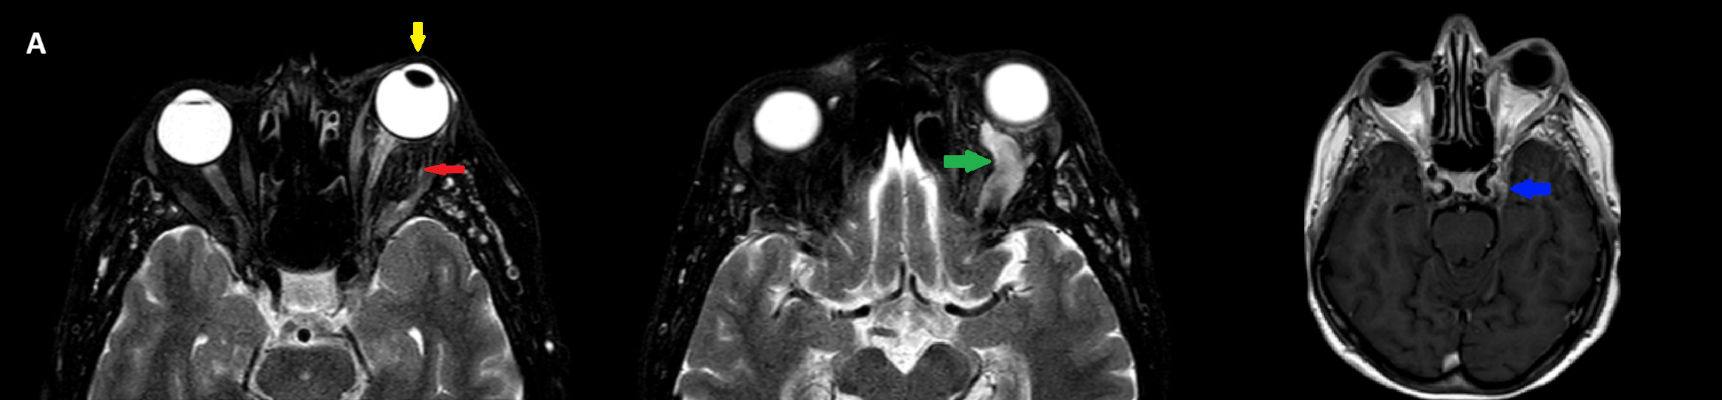

- A) Orbital MRG’de yağ baskılı T2A görüntülerde sol orbital globta ekzoftalmus (ok) izlenmiş olup retrobulbar yağlı dokuda kirlenmeler (ok) ve dilate superior oftalmik ven (ok) dikkati çekiyor. Beyin MRG’de kontrastlı T1A görüntüde sol kavernöz sinüste simetriğine oranla genişleme (ok) izleniyor.

- B) Pre ve post-kontrast yağ basklılı T1A görüntüler incelendiğinde superior oftalmik venin (oklar) kontrast madde verildikten sonra homojen dolum gösterdiği, dilate ve tortiyoze görünümde olduğu izleniyor.